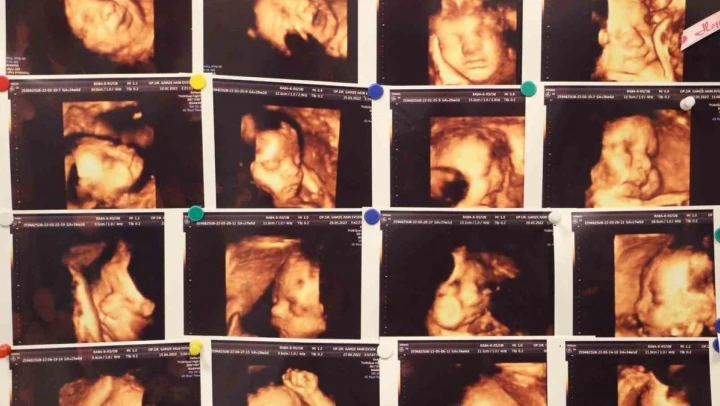

Tıbbi literatürde abortus yani düşük olarak tanımlanan gebelik kaybı, bebeğin 500 gram ağırlığına ulaşmadan veya 20'inci haftadan önce çeşitli sebeplerden ötürü gebeliğin sonlanması anlamına geldiğini açıklayan Dr. Evsen, genelde en sık ilk 3 aylık dönemde görülebilmekte olduğunu dile getirdi.

'Klinik olarak saptanan gebeliklerin yüzde 10-15'i düşükle sonuçlanmakla beraber bu durumun tekrar etmesi yani tekrarlayan gebelik kayıplarında oran Yüzde 3 ila 5'tir. Tekrarlayan gebelik kayıplarında en sık kromozomal sıkıntılar olmakla beraber, genetik anomaliler, hormonsal sıkıntılar, kan pıhtılaşması, rahmin yapısal bozuklukları, annede var olan diyabet ve guatr gibi sistemin hastalıklar, annede tekrarlayan enfeksiyonlar, bağışıklık sistemi sorunları ve çevresel faktörler görülebilmektedir.'